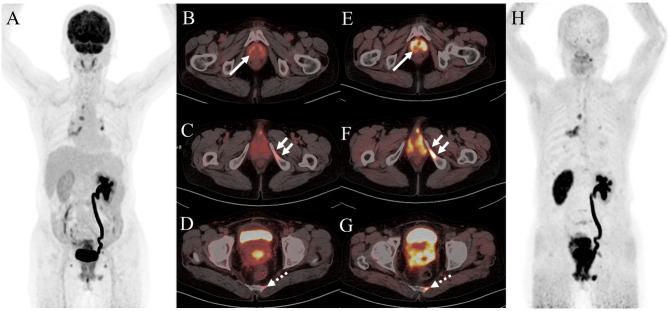

Fig. 3.

A 68-year-old woman was admitted to our hospital due to the discovery of a left axillary mass for over 10 days. The 18F-FDG PET/CT and 68Ga-FAPI PET/CT were performed for initial assessment. The MIP image(A) and the axial views of 18F-FDG PET/CT (B: PET image; C: CT scan; D: PET/CT fused image) showed suspicious lymph nodes in the right external iliac region (solid arrow, SUVmax, 8.8). However, it showed no corresponding uptake on 68Ga-FAPI PET/CT (E: PET image; F: CT scan; G: PET/CT fused image; H: MIP). Subsequently, the patient underwent lymph node puncture and pathological results revealed a small number of lymphocytes